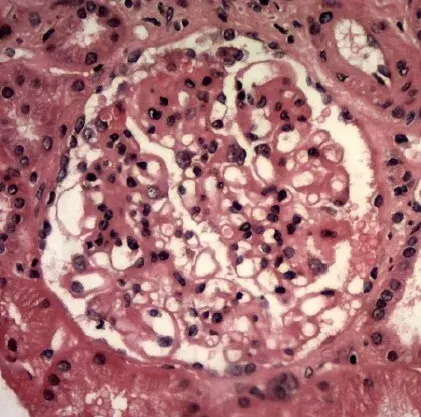

Caso clínico publicado en el **[NEJM](https://www.nejm.org/doi/full/10.1056/NEJMicm2213584?query=featured_nephrology)**: Un hombre de 35 años con nefropatía por IgA acudió a urgencias con síntomas de confusión mental, visión borrosa y convulsiones durante 1 día. Dos semanas antes de la presentación, comenzó a tomar ciclosporina para el tratamiento de la nefropatía por IgA. Su presión arterial era de 160/80 mm Hg.